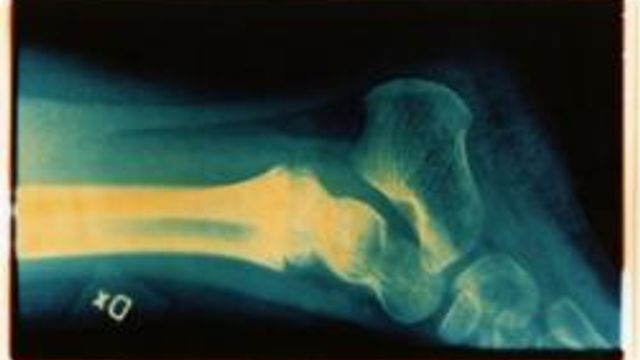

Quando l'osso non guarisce

Se l'osso non si ricompone le nuove tecniche prevedono anche l'impiego di fattori di crescita

Quando la frattura non guarisce intervengono le nuove tecniche ortopediche che comportano l'impiego di fattori di crescita, cellule staminali multipotenti, supporti di materiali sintetici o biologici. La nuova frontiera si chiama rigenerazione dei tessuti e le ultime novità sono state presentate a Milano in occasione del convegno della società scientifica europea Estrot.

, direttore del dipartimento di Ortotraumatologia e chirurgia specialistica dell'istituto G.Pini di Milano, ha spiegato: "Capita dal 6 al 9 per cento dei casi che le fratture non guariscano, non si riparino. Le cause sono diverse: una situazione di immunodepressione del paziente, un intervento non eseguito correttamente o un'infezione".

Per far fronte a queste situazioni gli ortopedici hanno realizzato la cosiddetta "terapia sartoriale" a misura di paziente. In base alla gravità dei casi vengono usate tecniche di ingegneria e rigenerazione dei tessuti diverse. Marelli continua: "Per esempio per ricostruire i tessuti usiamo cellule staminali multipotenti (mesenchimali stromali) come nuovi mattoni dell'osso da riparare. Queste si ottengono in sala operatoria in circa quindici minuti. Con una siringa ad hoc si aspira del tessuto midollare dal paziente, che poi viene preparato mediante centrifugazione. Queste tecniche sono sempre più impiegate nella pratica clinica, ma vanno usate in casi selezionati".